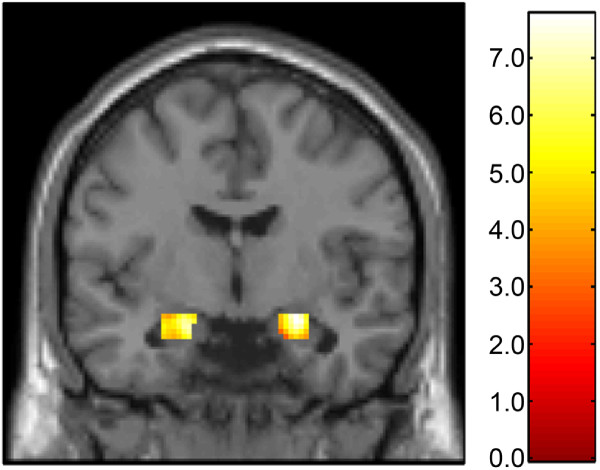

Background: The amygdala and medial prefrontal cortex (mPFC) comprise a key corticolimbic circuit that helps shape individual differences in sensitivity to threat and the related risk for psychopathology. Although serotonin (5-HT) is known to be a key modulator of this circuit, the specific receptors mediating this modulation are unclear. The colocalization of 5-HT1A and 5-HT2A receptors on mPFC glutamatergic neurons suggests that their functional interactions may mediate 5-HT effects on this circuit through top-down regulation of amygdala reactivity. Using a multimodal neuroimaging strategy in 39 healthy volunteers, we determined whether threat-related amygdala reactivity, assessed with blood oxygen level-dependent functional magnetic resonance imaging, was significantly predicted by the interaction between mPFC 5-HT1A and 5-HT2A receptor levels, assessed by positron emission tomography.

Results: 5-HT1A binding in the mPFC significantly moderated an inverse correlation between mPFC 5-HT2A binding and threat-related amygdala reactivity. Specifically, mPFC 5-HT2A binding was significantly inversely correlated with amygdala reactivity only when mPFC 5-HT1A binding was relatively low.

Conclusions: Our findings provide evidence that 5-HT1A and 5-HT2A receptors interact to shape serotonergic modulation of a functional circuit between the amygdala and mPFC. The effect of the interaction between mPFC 5-HT1A and 5-HT2A binding and amygdala reactivity is consistent with the colocalization of these receptors on glutamatergic neurons in the mPFC.